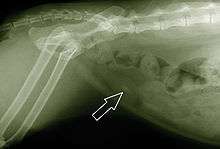

When symptoms indicate bladder stones, the first step is usually to take an x-ray. Most types of stones will appear readily in an x-ray, urate and occasionally cystine stones being the most common exceptions. Stones smaller than three millimeters may not be visible.[3] Ultrasonography is also useful for identifying bladder stones. Crystals identified in a urinalysis may help identify the stones, but analysis of the stones is necessary for identification of the complete chemical composition.